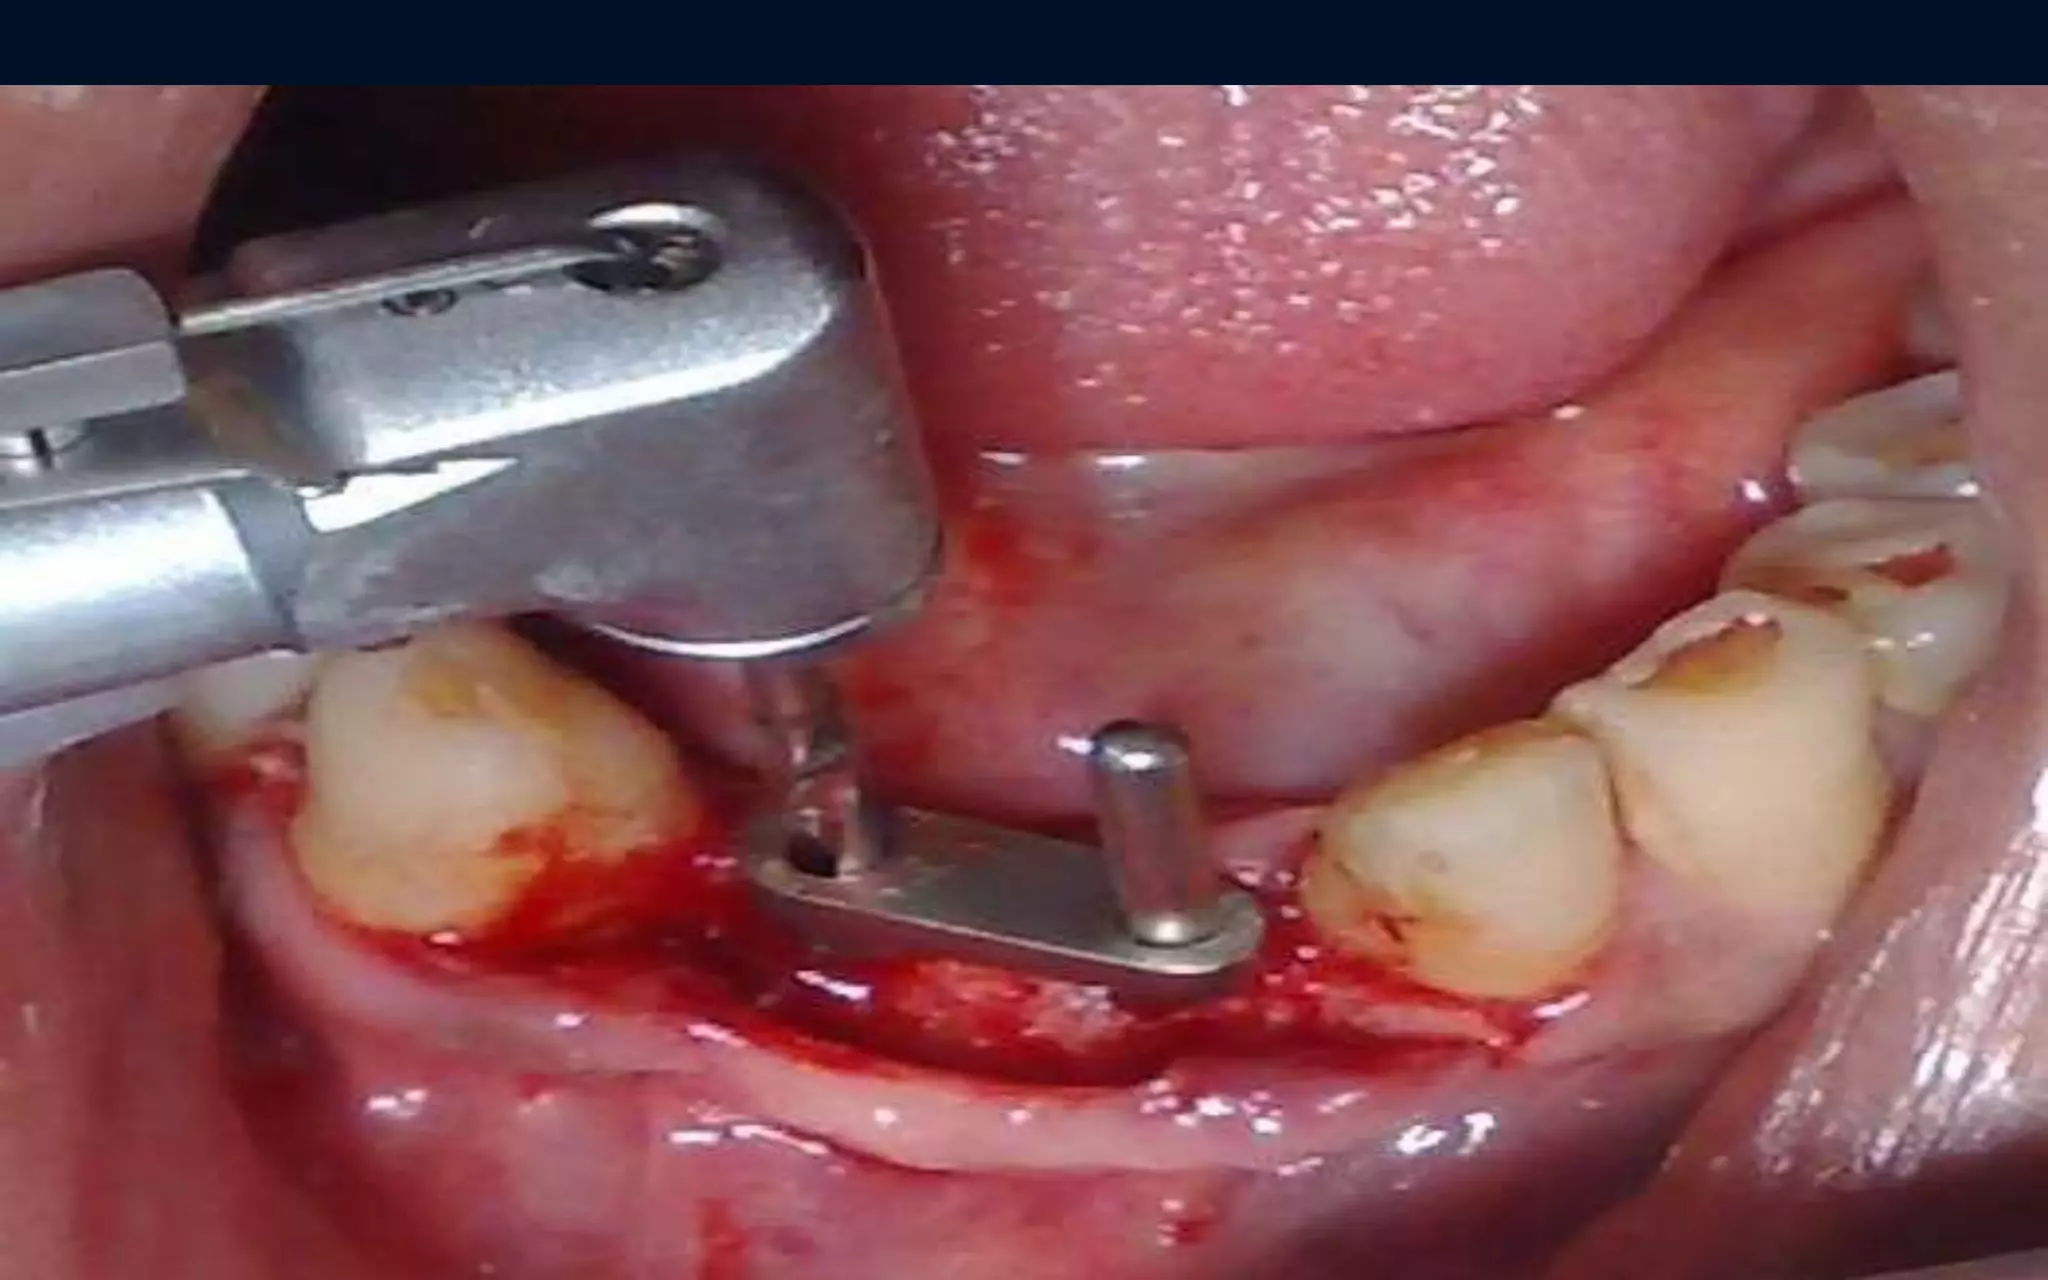

Surgical Phase

Milled abutment in

placed ( positioning

jig)